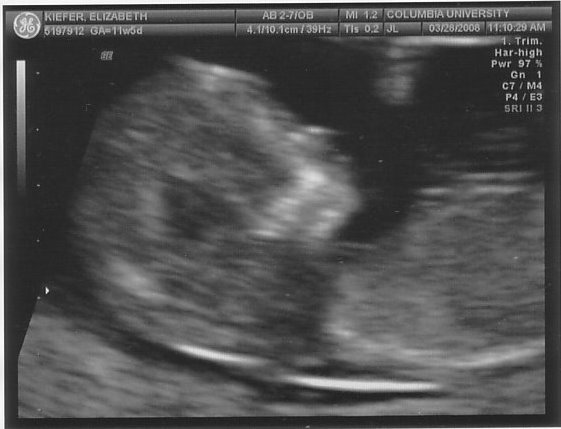

On Friday we headed uptown for our second ultrasound. Nobody told me that baby m0ves around in there at 12 weeks (thanks for the help, parenting books, keep up the good work!), so I just about freaked out when he arched his back and rubbed his face (or she/her, of course, we don’t find that out for another 6 weeks). Fortunately our tech was used to people gasping loudly. Sooooo cool.

In case you were wondering if I was going to be a stereotype of a dad, I’m including all 5 blurry blob pictures here. And if I had an hour long movie of same, I’d post that, too.